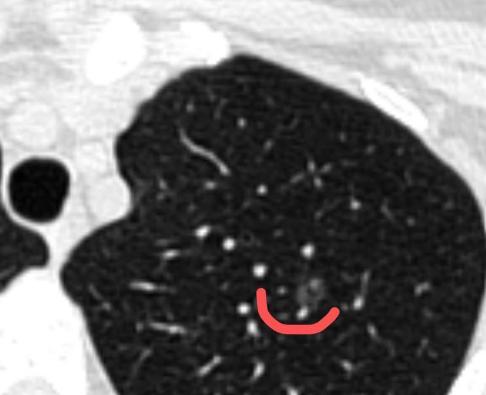

为了一个6mm的小结节,切掉一大块肺?如果是这样的手术,我坚决不做!今年38岁的吴女士体检发现了肺磨玻璃结节,虽然随访了一年都没变化,但问了好几位医生,大多提醒她:“结节中间有空腔,有一定风险,可能是肿瘤特征,建议手术切除肺叶。” 这句话让她陷入了长期的焦虑。那段时间,她吃不下、睡不好,连孩子都顾不上管,甚至出现了胸背痛、气促的症状,整天担心自己是不是晚期了、结节是不是要转移了。 后来她找到我,态度非常坚决:一定要手术,不管切多少肺都愿意做。 但我仔细看了她的片子,结节位置比较深,如果按常规做法切掉整个肺叶,对肺功能的影响不小。 所以我一开始还是建议她继续观察——毕竟结节没变化,通常意味着风险很低。 可她和家人反复联系我,几次来门诊,都坚持要做手术。我理解她的心情,这种“身体里有个东西”的感觉,确实像心里扎了根刺。 于是我跟她商量:不如我们做个三维重建,仔细看看结节的位置和血管走向,说不定能设计一个既切得干净、又不用切那么多肺的手术? 毕竟生命不只有长度,生活质量也很重要...... 三维结果出来之后,我发现可以做“亚段切除”——也就是只切除肺段的一小部分,范围非常精准,创伤也小得多。 术后病理结果是“不典型腺瘤增生”还是属于癌前状态。它有可能随着时间慢慢变化,甚至发展成原位癌或早期腺癌,但这个过程非常缓慢,通过定期随访完全可以安全监控。即便有变化再处理,也完全来得及。 而吴女士之前那些胸痛、气短的症状,其实更多是焦虑引起的身体反应。手术后她恢复得很好,查房时她跟我说:“医生,我现在安心了,心里的‘定时炸弹’终于拆掉了。” 通过这个案例,我也想和大家分享两点: 1、对于这种小的磨玻璃结节,定期随访是非常安全的,不必过度紧张; 2、如果实在焦虑到影响生活,可以考虑做创伤小的精准手术,但为了一个小结节去切掉整个肺叶,我个人认为还是要慎重。[玫瑰][作揖]胸外科乔贵宾医生肺结节[超话]